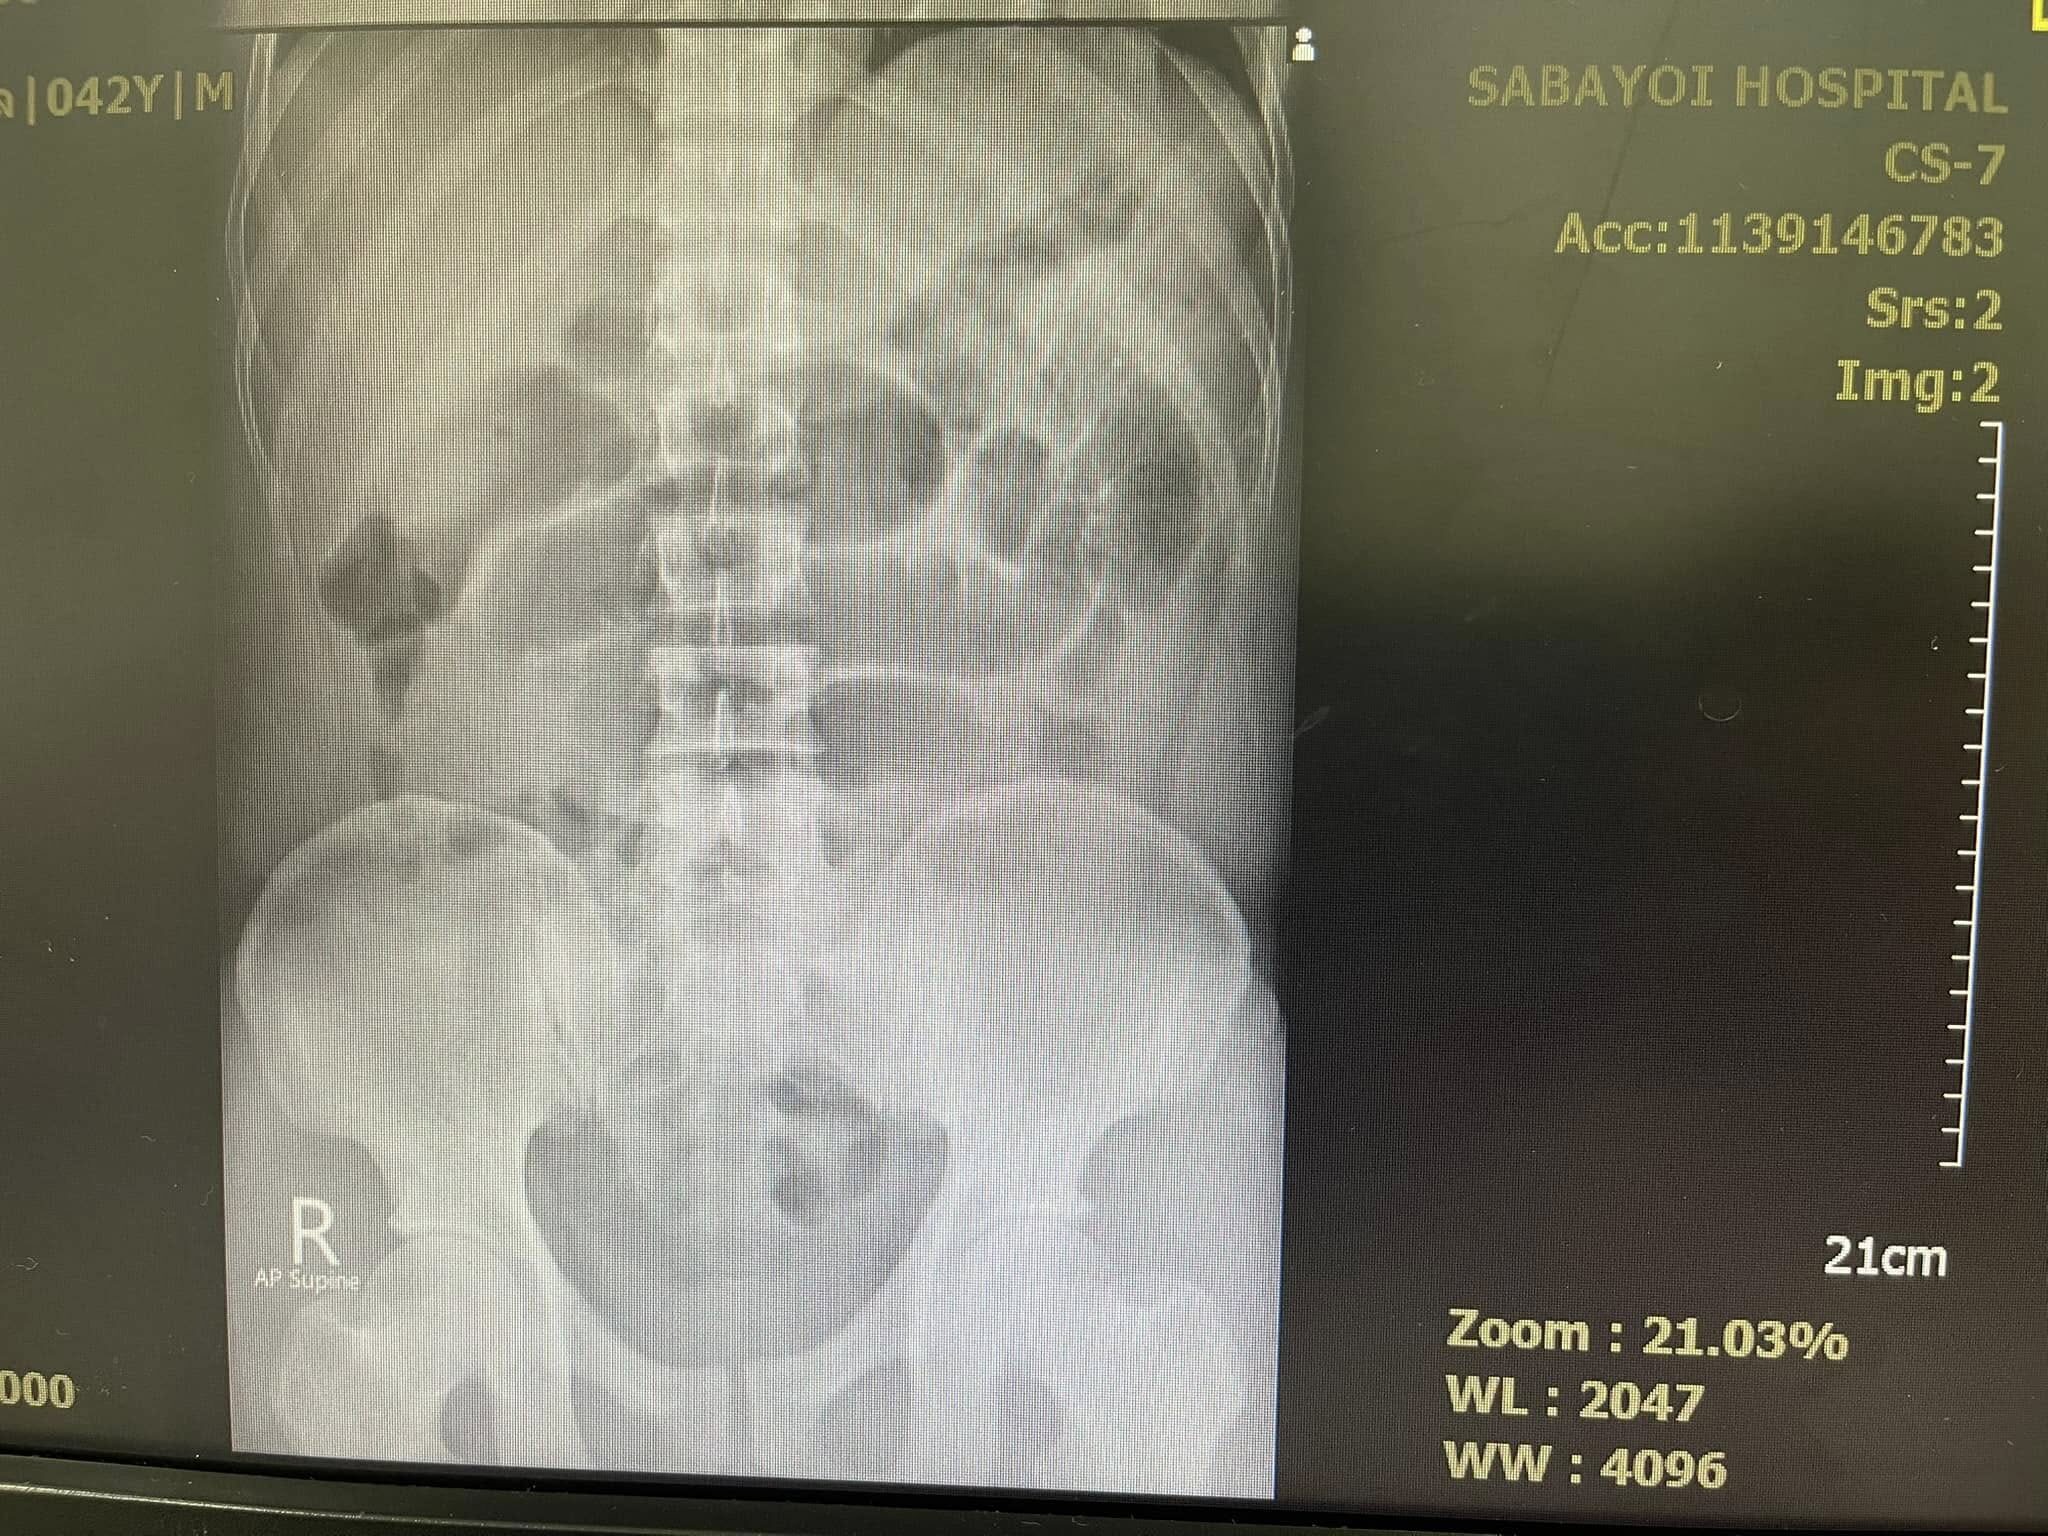

คนไข้อายุสี่สิบเศษ กินน้ำท่อม ทุกวันมา 4-5 ปี ปวดท้องจึงมาโรงพยาบาล ผมคลำแล้วก็พบว่าท้องอืดๆ ให้ไปเอ็กซเรย์ กลับมาภาพสวยเหมือนในตำรา พบว่ามีภาวะลำไส้อุดตัน จึงให้นอนโรงพยาบาลใส่สายยาง NG tube เข้ากระเพาะต่อกับเครื่องดูดลมออกจากกระเพาะ ถ้าดีขึ้นลำไส้คลายตัวก็โล่งไป ถ้าไม่ดีก็ต้องส่งไปผ่าตัด

รายนี้ยืนยันกินแต่น้ำท่อม ไม่ได้กินใบท่อมสดๆ (ปกติลำไส้อุดตันมักพบในคนกินใบกระท่อมสดๆ) ไม่เคยมีประวัติผ่าตัดใดๆ